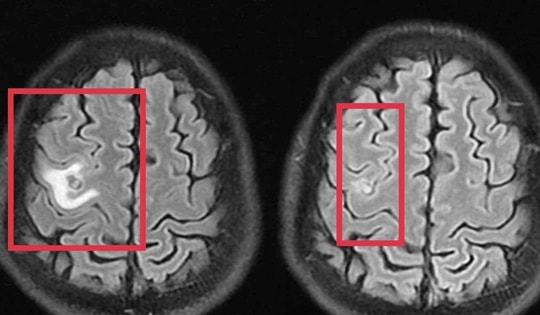

Cháu bé đau tai dữ dội, bác sĩ sốc ngang phát hiện bí mật "đáng sợ" bên trong